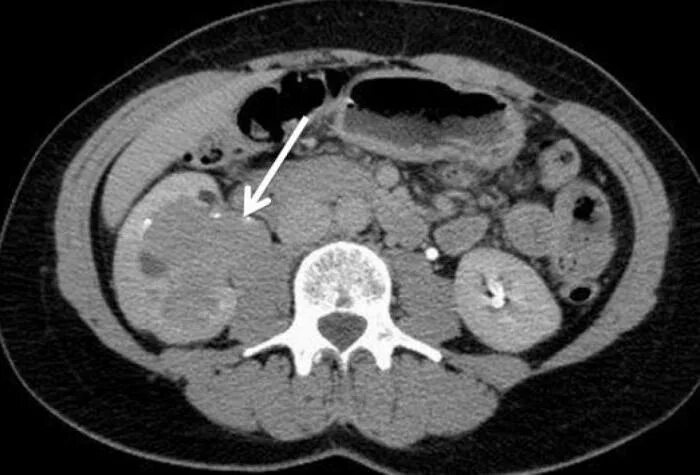

Метастазы рака почки